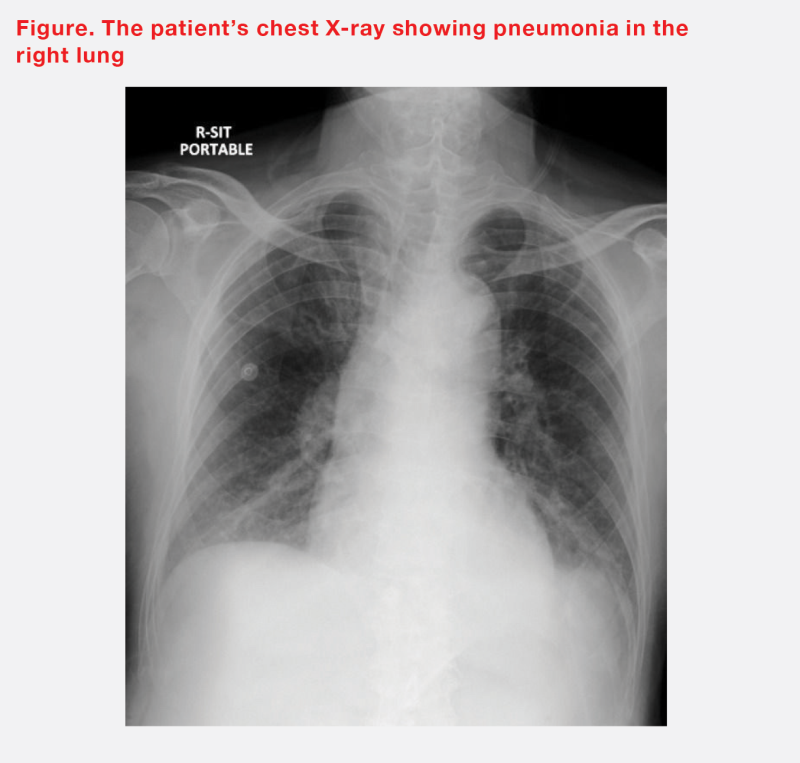

Chest X-ray revealed signs of heart failure (HF) as well as pneumoÂnia in the right lower and right upper zones of the patient’s lungs. (Figure) Respiratory sample tested positive for respiratory syncytial virus (RSV) on polymerase chain reaction assay. The suspected superimposed bacteÂrial infection causing pneumonia was managed with antibiotics.